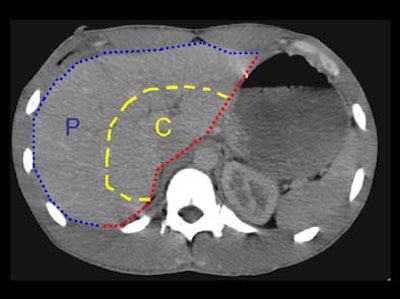

"This (division) is arbitrary, but the central area of the liver we took to represent the hilum, the area where the main bile ducts and blood vessels are coming through, and tried to distinguish that from the peripheral aspects of the liver," Lucey said. "We also decided whether the liver lacerations extended to the medial or lateral edge of the liver, or both. All active bile leaks were documented on HIDA scans.

| The liver was divided into sections for the study. The red line represents the medial surface of the liver. The blue line represents the peripheral surface (P) of the liver. The yellow line roughly separates the peripheral from the central part (C) of the liver. All images courtesy of Dr. Brian Lucey. |

"The reason this is important is that it means you can have a laceration involving the medial and lateral surfaces, but it will remain a peripheral laceration rather than extending to the central portion of the liver," he said.